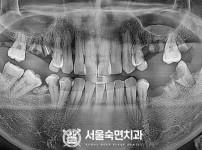

임플란트-전후사진3